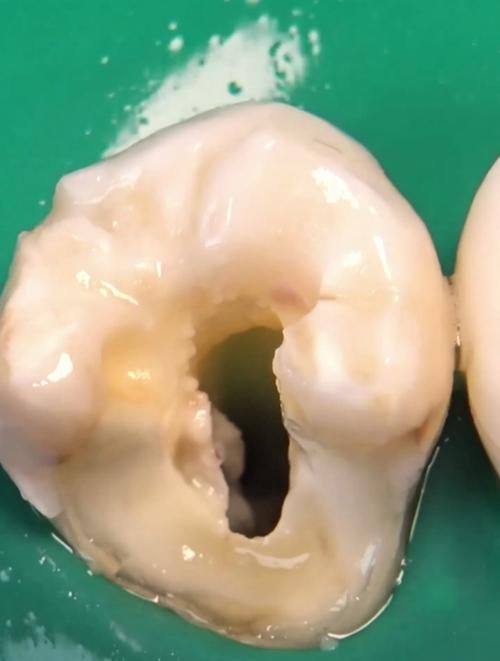

要是牙齿已经形成了实质性缺损,树脂填充就是常用的治疗方法。治疗过程中,医生首先会去除龋坏组织,就像把坏掉的“零件”拿掉。同时,还会去除失去支持的薄弱牙体组织,让牙齿更加稳固。然后,医生会按照要求将龋洞制备成合理的形态,这就像是为填补材料打造一个合适的“家”。末尾,用复合树脂填充龋洞,让牙齿修复原来的形态和功能。树脂材料的颜色和牙齿特别接近,填充后几乎看不出来,既美观又实用。